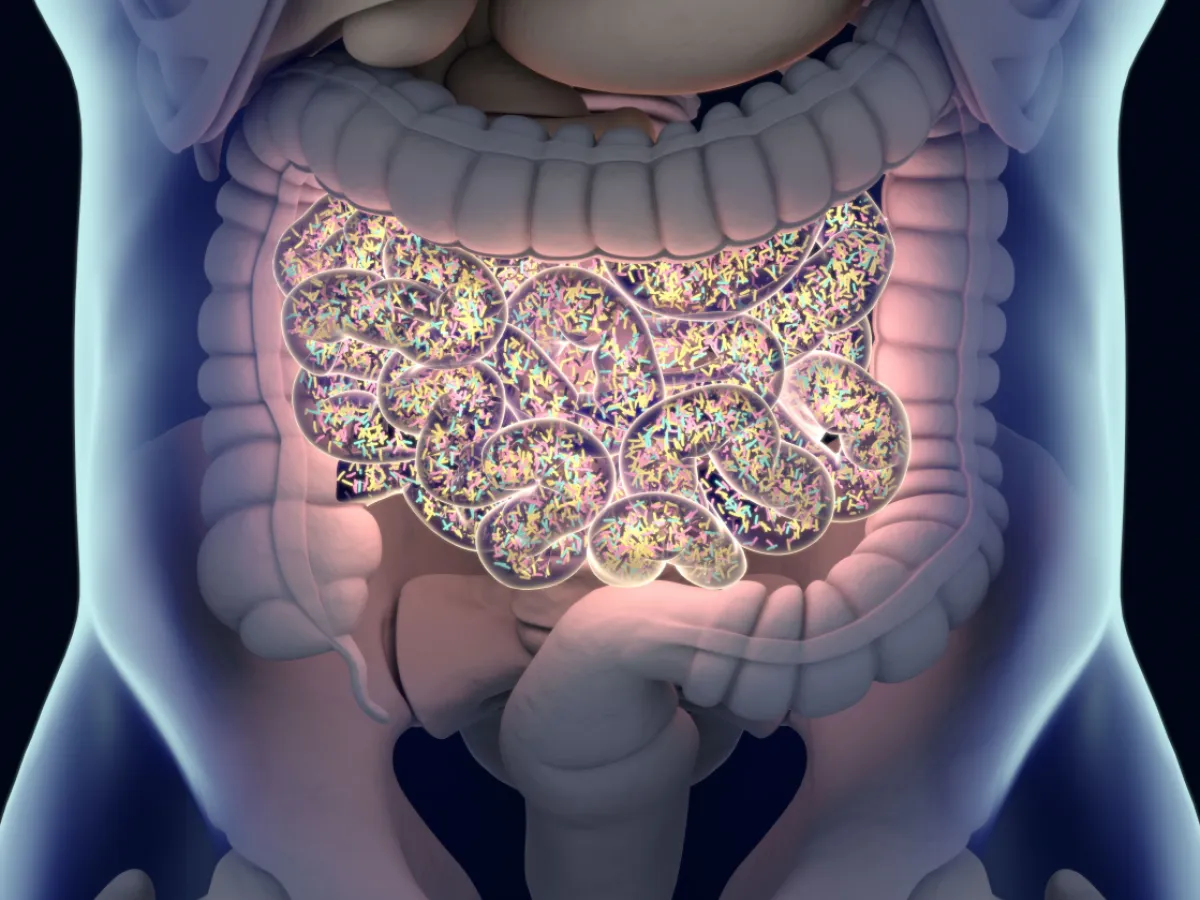

The human gut microbiome – a bustling community of trillions of microorganisms – is increasingly recognized as a cornerstone of overall health. Recent research, spearheaded by Pyry Sipilä of the University of Helsinki, is shifting our understanding from simply what microbes are present to how they interact. This dynamic perspective opens exciting possibilities for manipulating these microbial neighborhoods to improve well-being.

For years, microbiome research focused on cataloging the diverse species inhabiting our guts. However, Sipilä’s work emphasizes that the overall network structure and the strength of interactions between key species are more critical than simply identifying which microbes are present. These “strongly interacting species” act as control points, shaping the behavior of the entire ecosystem. Even if not the most abundant, their influence is disproportionately large.

The implications for human health are profound. The microbiome influences digestion, immunity, and even mental health. Understanding these dynamics paves the way for personalized medicine, where treatments are tailored to an individual’s specific microbial ecosystem. Instead of a one-size-fits-all approach, interventions could focus on manipulating the key species that control community structure.